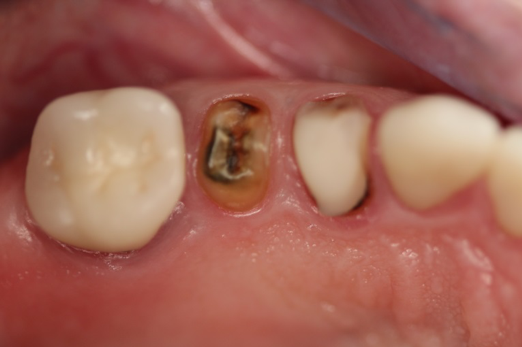

Fig 10. Preoperative panoramic radiograph.

Figure 10

Fig 11. Preoperative healed sites.

Figure 11

Figure 10 through Figure 13 show the preoperative x-ray and the sequence of beginning with healed sites through the surgical placement of the implants. The implants were protected by an Essix-style wound-protection removable retainer for approximately 12 weeks. After the integration phase, the implants and the natural dentition were prepared using traditional crown-and-bridge high-speed diamond and zirconia cutting burs to remove decay and existing restorative materials, to complete and refine the natural-tooth structures to receive full-crown coverage, and to prepare and refine gingival margins of the zirconia implants where needed.